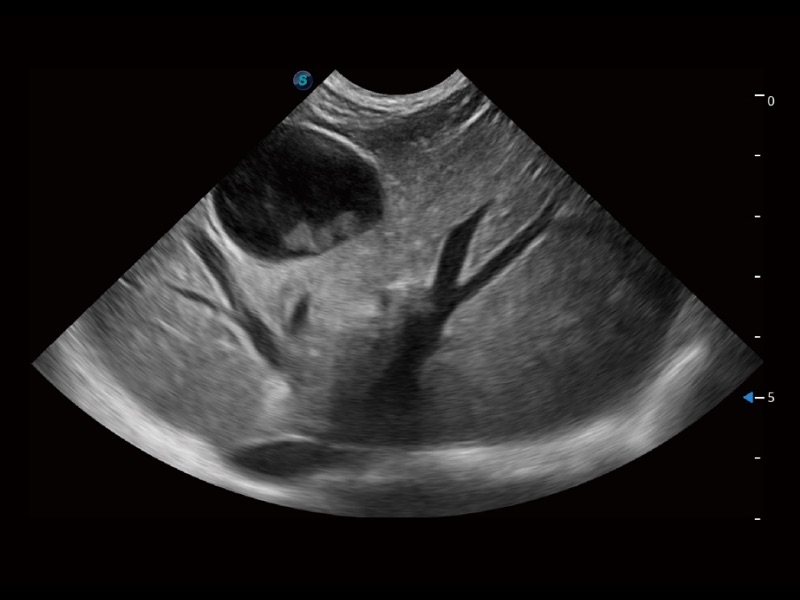

通过色彩血流和实时宽景相结合,可观察到完整的静脉或动脉的血流,方便医生检查。实时扫查过程中,如有任何操作失误也可以很容易地进行回扫擦除,而不会中断扫查。